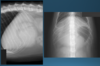

What is shown in these images?

canine acute gastric dilation

-pylorus is still in the normal place; right and more ventral